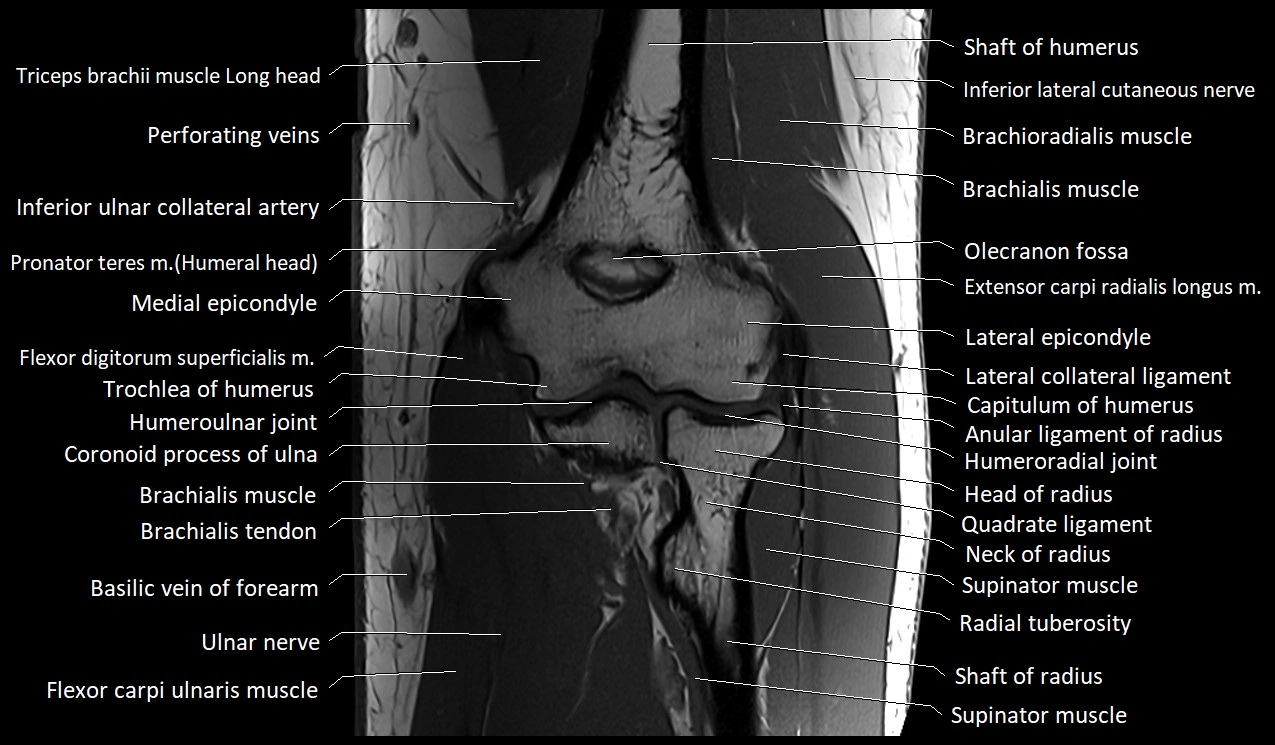

MRI image

image